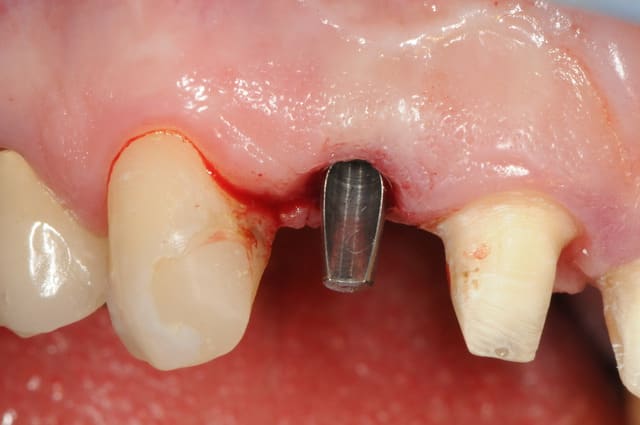

je jour J, à l'heure H, je fini par poser mon implant.

il reste même après deux mois encore des saletés (photo2)

photo

3- axe implantaire

4-5 pose implant et comblement